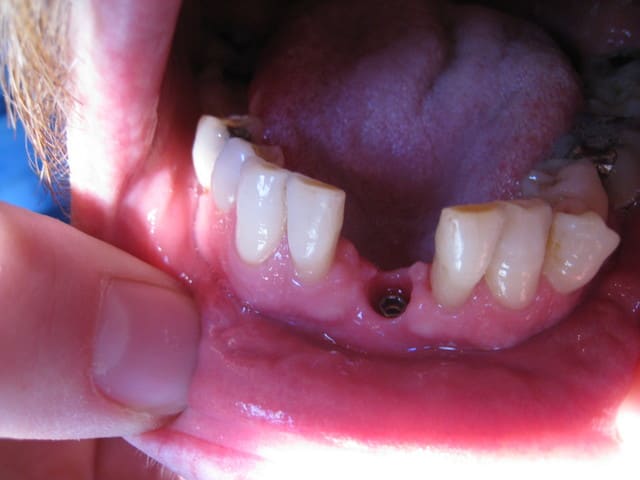

Hello

Un compromis pour remplacer 2 centrales 31-41

Voilà c'est mon 1er post !!